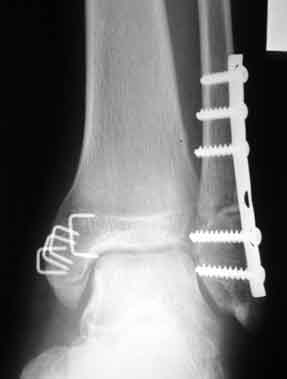

八瀬リーダーの足のレントゲン写真です。 1年半以上経った今でも金属片は足に入っているそうです。 飛行機に乗るときは、かならずこの写真のコピーを持って行くようにしているのだそうです。 なぜかって? それは、金属探知器に引っかかった時の対策になるからです。 (特に外国の空港で引っかかったら洒落にならなくなりそう・・・) 怖くなった人ご免なさい。 かなり悪趣味なページでした。 補足: この写真は本人の承諾の上掲載しました。

補足: この写真は本人の承諾の上掲載しました。